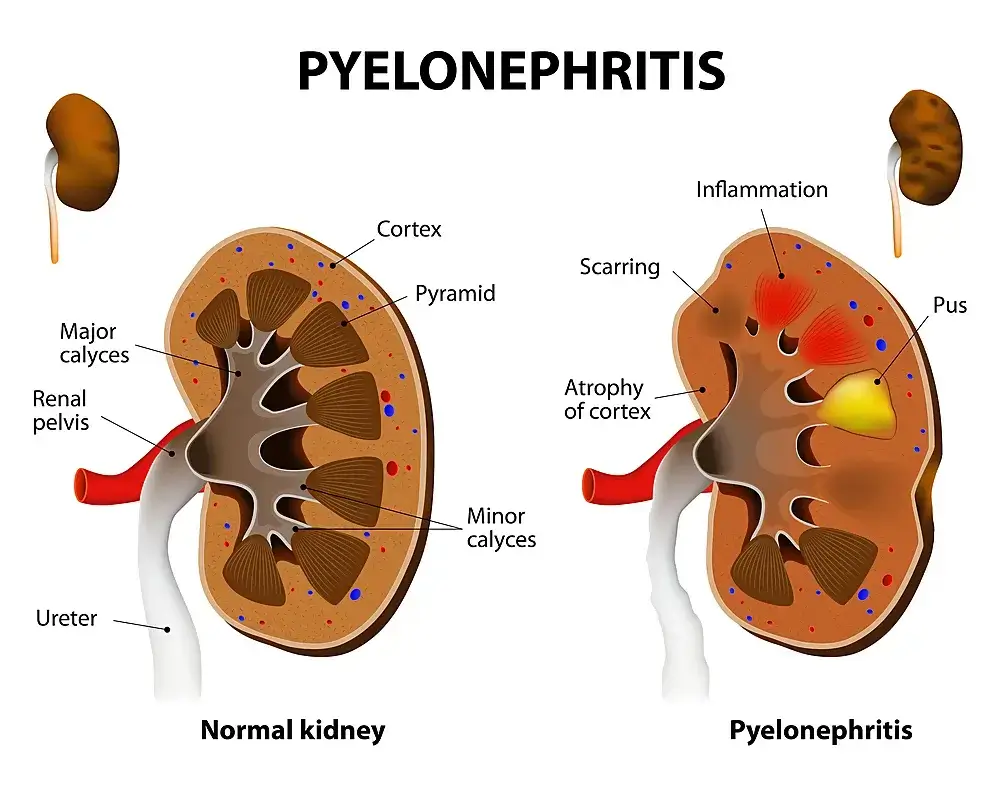

Pyelonephritis

Pyelonephritis is a serious kidney infection caused by the bacterium Pseudomonas aeruginosa. It is most common in people who are hospitalized or have a weakened immune system, but it can also be contracted from contaminated water, soil, or saliva. Symptoms of pyelonephritis include fever, chills, headache, and weakness.

If not addressed, pyelonephritis can lead to permanent kidney damage. Pyelonephritis is an infection of the kidneys and can be caused by a variety of bacteria. Pyelonephritis is most common in people age 65 or older and is more common in men than women.